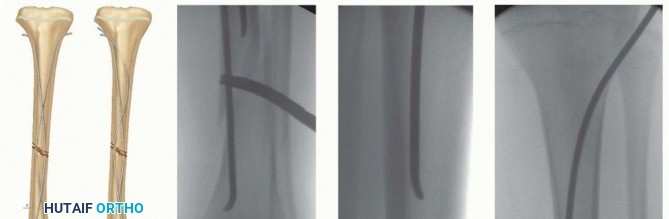

Preparation for Nail Insertion

The nails are inserted in the tibial metaphysis.

The proper starting point is at least 1 cm distal to the proximal tibial physis and 2 cm posterior to the tibial tubercle physis (

TECH FIG 3A,B

).

The relevant landmarks should be identified fluoroscopically and marked on the skin (physis, tubercle, starting points) before proceeding (

TECH FIG 3B

The incision should be 1 to 1.5 cm long, with its most distal extent roughly 1 cm proximal to the physis.

This will allow an oblique passage of the nail at the correct proximal to distal angle.

A small hemostat is used to carefully spread through the tissue down to bone, and a drill sleeve and drill are placed on the bone. The drill should be 1 to 1.5 mm larger than the diameter of the nail.

TECH FIG 3 • A. The proper starting point for nail insertion lies at least 1 cm distal to the proximal tibial growth plate and 2 cm posterior to the tubercle physis. B. Patient undergoing elastic intramedullary nailing of the tibia. Marked on the skin are the proximal growth plate and proposed entry sites as well as the fracture. The incision is made proximal to the line of the physis, and an oblique angle matching the final path of the nail is dissected with a hemostat down to the bone. C. After confirming the entry site radiographically, a drill is used through a guide to open the cortex 1 to 2 mm larger than the nail diameter. D. The drill starts perpendicular to the bone and is advanced distally. Care is taken not to drill into a previously placed nail or through the far cortex.

After checking the position of the drill tip with fluoroscopy (

TECH FIG 3C

), a starting hole is drilled along the proposed path of the nail (

TECH FIG 3D

Care is taken not to drill across the tibia out the opposite cortex.

Alternatively, an awl can be used by hand to create this opening in the cortex.